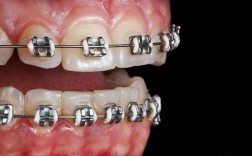

口腔正畸摄影常用类型及临床意义

| 摄影类型 | 临床意义 | |

|---|---|---|

| 口内全牙列照 | 上/下颌全牙列,显示牙齿排列、咬合关系及牙弓形态 | 评估牙列拥挤/间隙、咬合异常(深覆合、锁合)及牙弓对称性 |

| 口内后牙咬合照 | 上下后牙颊侧咬合面,显示尖窝关系 | 判断后牙咬合功能及尖牙保护是否存在 |